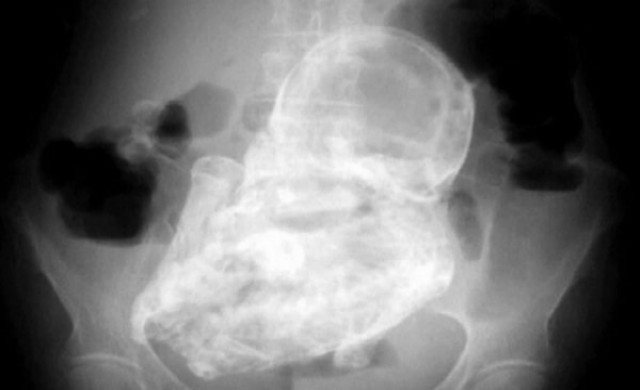

แหล่งข่าวการแพทย์ เผยเมื่อวันศุกร์ ว่า ซากทารกน้ำหนักเกือบ 2 กิโลกรัม ถูกค้นพบหลังจากคุณยายถูกนำตัวส่งโรงพยาบาล เพื่อรักษาอาการบาดเจ็บจากการหกล้ม และผลการเอ็กซ์เรย์ตรงส่วนตะโพก พบทารกในครรภ์ซึ่งถือกำเนิดได้ประมาณ 7 เดือน ในสภาพแข็งเป็นหิน เนื่องจากถูกเกาะด้วยแคลเซียม แต่ไม่ได้ทำให้คุณยายเกิดอาการเจ็บปวดใดๆ

สภาวะที่หาได้ยากดังกล่าวนี้ เรียกกันว่า Lithopedian หรือ เด็กหิน เกิดขึ้นเมื่อทารกเสียชีวิตระหว่างการตั้งครรภ์ และแคลเซียมเกาะจับจนแข็งเป็นหินนอกมดลูก กรณีเช่นนี้มีให้เห็นเพียงหลักร้อยต้นๆ ในประวัติศาสตร์ของวงการแพทย์ทั่วโลก และไม่ใช่เรื่องผิดปกติแต่อย่างใด ที่ภาวะเช่นนี้จะไม่ถูกตรวจพบ ในเวลานานหลายสิบปี